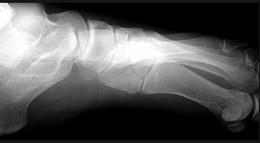

问题 女,25岁,扭伤后足中部痛,结合图像,最可能的诊断是 ( )

选项 A、中间楔状骨骨折 B、未见异常 C、外侧楔状骨骨折 D、足舟骨骨折 E、內侧楔状骨骨折

答案 E